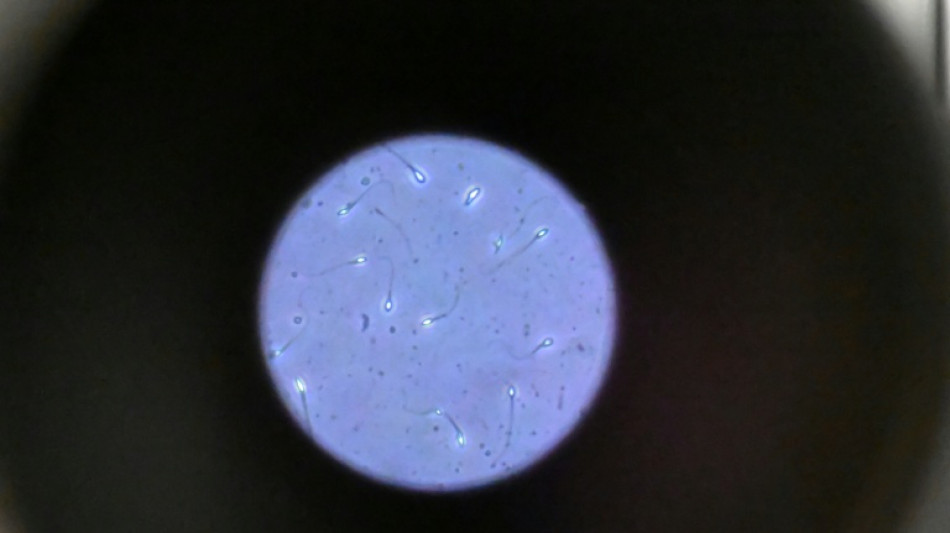

Sierra Leone: le drame sans fin des avortements clandestins face à une dépénalisation bloquée

Perdue et terrorisée, Mary a dû avoir recours à une guérisseuse en Sierra Leone pour mettre fin à sa grossesse alors qu'elle n'était encore qu'une adolescente, une épreuve qui lui a laissé des douleurs récurrentes et un traumatisme vécu encore par de nombreuses femmes dans ce pays.